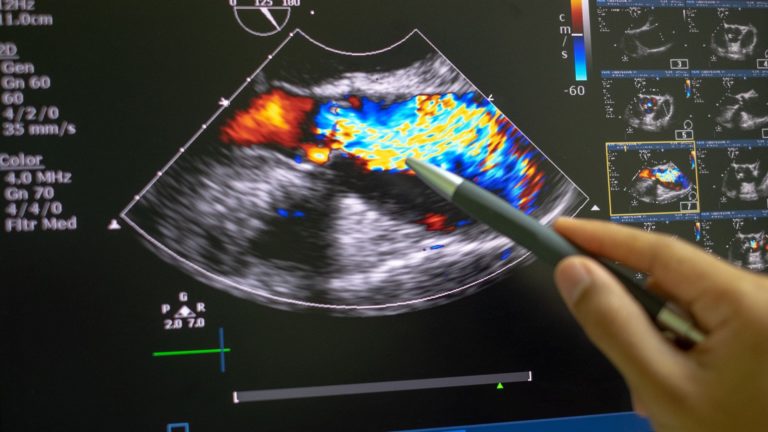

¿Qué significan los diferentes colores en una ecografía?

Se muestran diferentes colores según cómo las ondas sonoras se reflejan en una sustancia. La mayoría de las imágenes son en blanco y negro, pero notarás diferentes tonos en una ecografía. Los diferentes tonos representan las ondas sonoras que pasan a través de materiales de distintas densidades o se reflejan en ellos.

Tradicionalmente, las imágenes de ecografía eran en tonos de blanco, negro y gris. Un avance en la ecografía médica fue la llegada del Doppler en color. Usando esta nueva técnica, los profesionales de la salud pudieron observar directamente el flujo sanguíneo, particularmente dentro del corazón. Los colores representan la dirección y la velocidad del flujo sanguíneo en un área específica.

El naranja es posible cuando se utilizan máquinas de ecografía Doppler de potencia. Se usa para analizar el flujo lento. Si ves el color naranja, generalmente indica vasos sanguíneos.

¿Qué significan el rojo o el azul en una ecografía?

Los colores rojo y azul representan el movimiento de la sangre. El azul representa el flujo sanguíneo alejándose del transductor, mientras que el rojo representa el flujo sanguíneo hacia el transductor.

Si la pantalla muestra una combinación de azul y rojo, podría indicar flujo circular, flujo coherente o turbulencia.

Diferentes tonos de azul y rojo indican la velocidad. Los tonos más claros muestran una mayor velocidad, y los tonos más oscuros indican una velocidad menor.